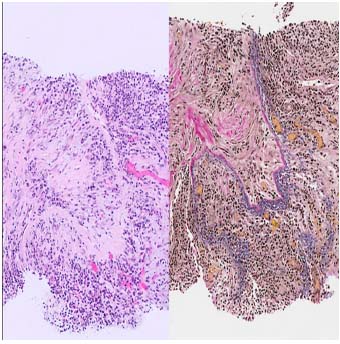

IgG4関連疾患の主な組織病理学的特徴 (文献 1)より)

| 組織学的所見 | 特徴 | 組織学的顕微鏡写真 |

|---|---|---|

| 閉塞性静脈炎 | 中小規模の静脈は密なリンパ形質細胞性炎症によって浸潤して狭窄し、場合によっては内腔の完全な閉塞につながります(左:HE染色、x100)。EVG染色(右、×100))は血管壁の破壊を示し、閉塞性静脈炎を確認します(右)。この所見はIgG4関連疾患に特徴的ですが、常に存在するとは限りません。 | ![]() |